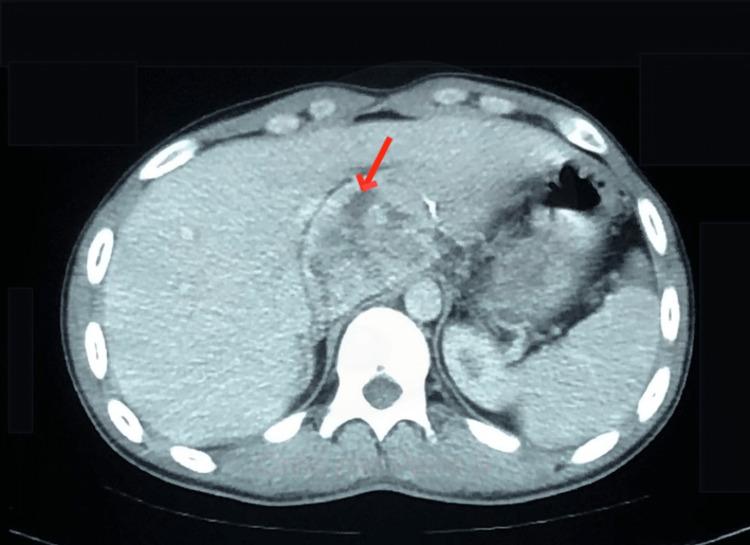

A pheochromocytoma is an uncommon tumor that originates from the chromaffin cells of the adrenal medulla. Also, adrenal tissue not located in its typical position is referred to as ectopic adrenal tissue. It is relatively uncommon in adults and is usually asymptomatic. Therefore, a pheochromocytoma arising from ectopic adrenal tissue is even a rarer finding and presents as a unique diagnostic challenge. A 20-year-old man presented with vague abdominal pain, and upon imaging, a mass located behind the liver was initially discovered. Subsequently, it was identified as a mass growing in an ectopic adrenal gland. He underwent exploratory laparotomy and resection of the mass. A pheochromocytoma in an ectopic adrenal gland was confirmed by histopathology.

摘要

嗜铬细胞瘤是一种起源于肾上腺髓质嗜铬细胞的罕见肿瘤。此外,位于非典型位置的肾上腺组织被称为异位肾上腺组织。它在成年人中相对少见,通常无症状。因此,起源于异位肾上腺组织的嗜铬细胞瘤更是罕见,是一个独特的诊断挑战。一名20岁男性因腹部隐痛就诊,影像学检查最初发现肝脏后方有一个肿块。随后,该肿块被确定为在异位肾上腺中生长。他接受了剖腹探查并切除了肿块。组织病理学证实为异位肾上腺中的嗜铬细胞瘤。